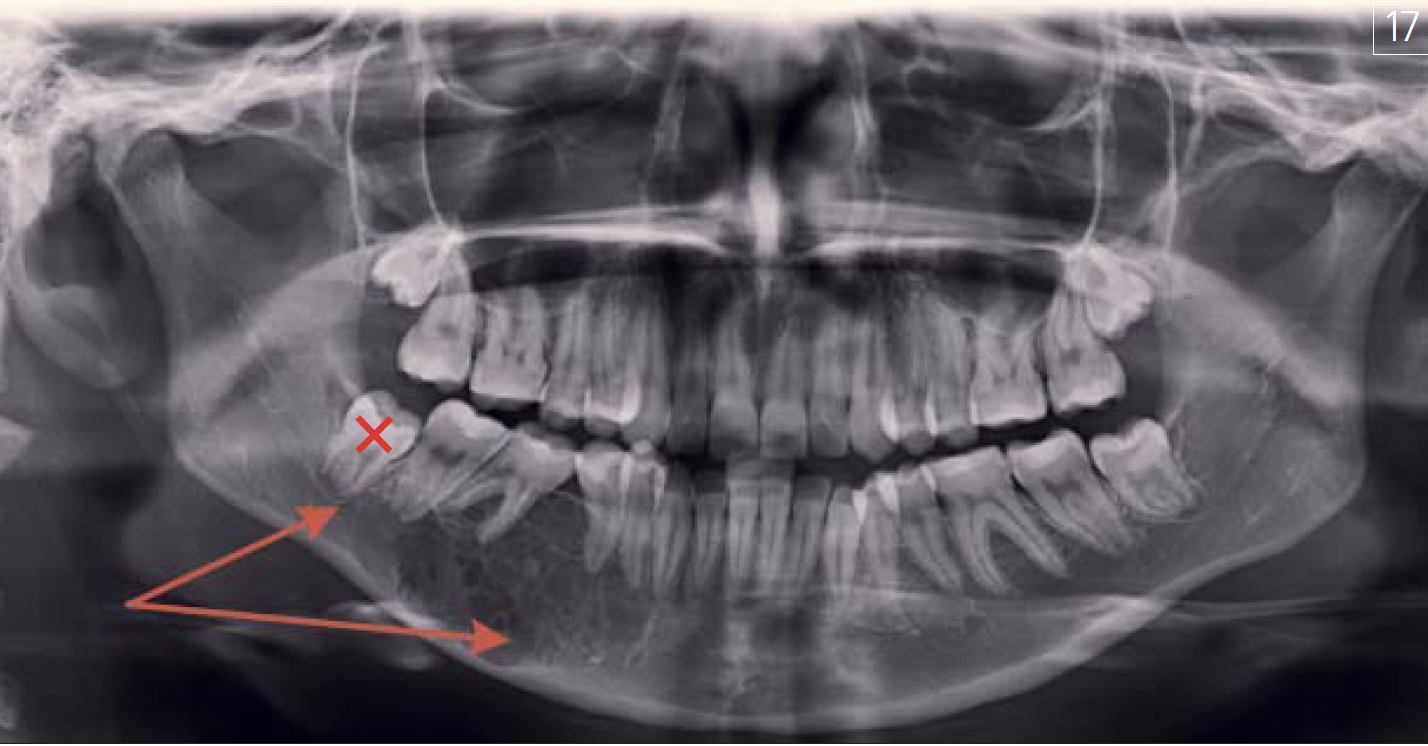

Особое место в практике врача-стоматолога, челюстно-лицевого хирурга и рентгенолога занимают ятрогении (рис. 13 а-в; 14 а, б; 15 а-в; 16; 17).

Рис. 17. Ортопантомограмма (стоматологом-хирургом амбулаторно удален зуб 4.8, прилежавшийк внутрикостной гемангиоме, указанной на рисунке красной стрелкой)